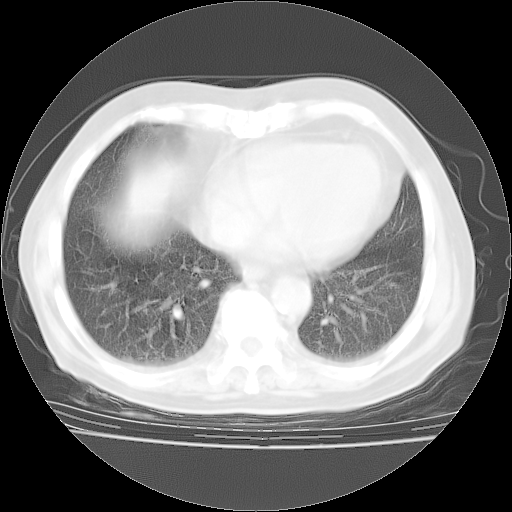

4月28日肺部CT——再次出现类似去年5月9日——磨玻璃样、间有“粟粒样”改变。

4月28日肺部CT——再次出现类似去年5月9日——透光度降低,“间质性”改变。

个人阅读4.14日肺部CT平扫:纵隔窗无异常,但肺窗示:双下肺内、后基底段有片絮状侵润影,部位以后基底段为著,以间质改变为主,呈急性肺泡炎征像,和首次住院影像学有相似之处。仅是个人读片,明日请相关专家再读片哈。其它建议同上。

1、108#的是4月14日的胸部CT(发此贴时还没看着28日的CT)。14日的胸部CT其实已经出现改变(如108#所述),个人认为28日的胸部CT除纵膈窗疑似有双侧胸膜增厚或少量胸积液(可行胸部B超明确)外,与4月14日对照病变有所加重;2、已经给予“异烟肼、利福平、乙胺丁醇”抗痨治疗?如果是,甲强龙80mg可缓慢减量;如果环磷酰胺已停用,暂不使用;3、中性粒细胞92%,明显升高,目前体温情况?注意合并细菌感染可能,使用左氧氟沙星情况下,是否联用B-内酰胺类抗菌药物?另外是查免疫全套非风湿全套。

今请临免主任会诊后认为:4月14日胸部CT已有双下肺间质性改变。患者病情复发多系激素减量过快不正规所致。目前甲强龙80mg/日,一周后酌情开始减量,不易过快。环磷酰胺若已停用,暂不使用。他同意目前抗菌药物使用,但应考虑是否加用B-内酰胺类抗菌药物(中性细胞明显增高);2、结核复发目前依据不足;3、若免疫全套各项指标正常,考虑多系特发性肺间质炎可能大。4、加强支持,并注意保护胃黏膜。

今上午去请教了临免、呼吸主任:1、介绍病史和阅读系列胸部CT一致认为:患者肺结核不考虑,仍为肺间质纤维化,目前处于急性肺泡炎阶段。2、若仍发热,可将甲强龙增至:80mg Bid静滴,同时鉴于中性增高,合并细菌感染可能,继续左氧氟沙星治疗,再联用B-内酰胺抗菌药物,如头孢哌酮--舒巴坦;3、停用抗痨药;4、目前甲强龙每日剂量160mg ,体温正常后再酌情减量;目前暂不用免疫抑制剂;4、不建议使用免疫增强剂等;5、加强支持治疗,鼓励患者进食;5、注意随访肝、肾功及血常规情况;6、因患者目前激素用量较大,加用胃黏膜保护剂,防止消化道出血可能。